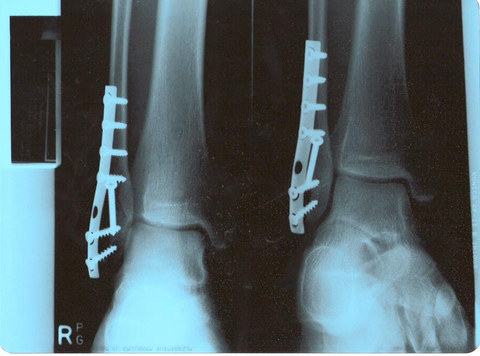

I haven't skated again since I broke my ankle at the beginning of the year. And I don't eblieve I have seen that